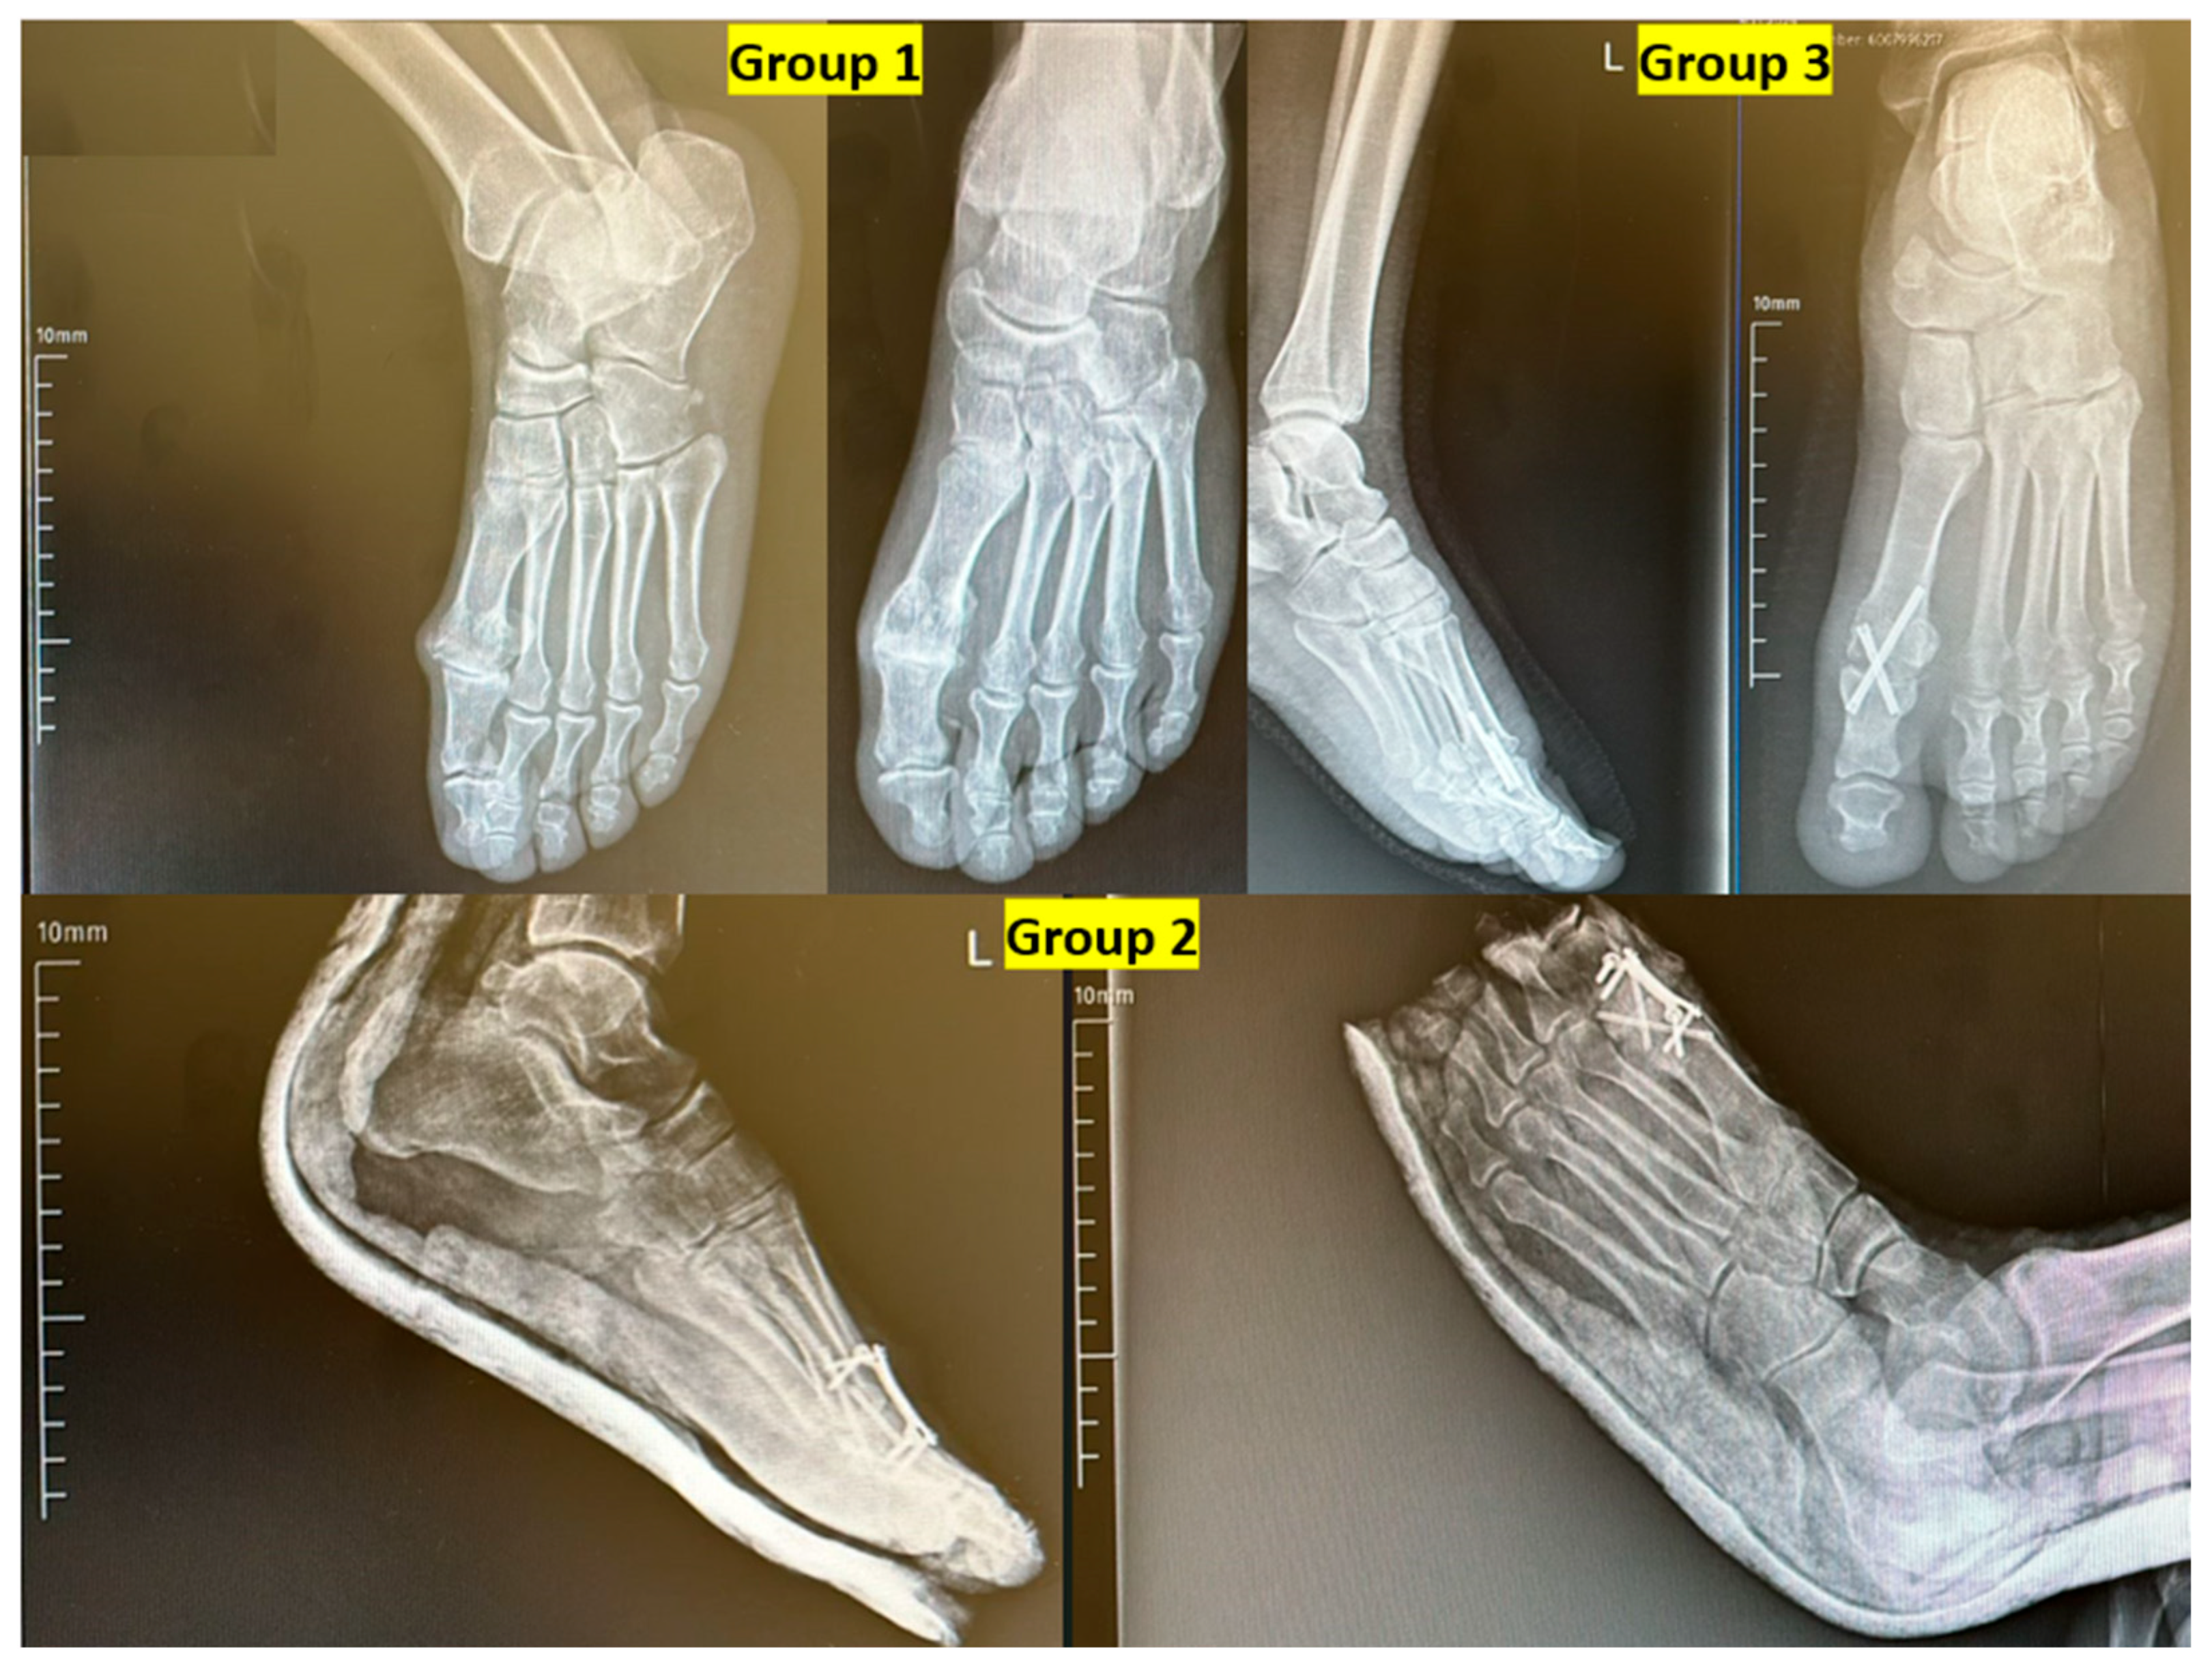

Patients were divided into three groups according to the type of fixation method used:

Group 1: Dorsal locking plate fixation (n = 19)

Group 2: Crossed cortical screw fixation (n = 16)

Group 3: Combined dorsal locking plate and crossed cortical screw fixation (n = 17)

The American Orthopedic Foot and Ankle Society (AOFAS) score and Foot Function Index (FFI) were collected using validated Turkish-language versions of the questionnaires, administered in an interview format by a trained orthopedic resident at follow-up visits [12]. Postoperative radiographic evaluations were conducted using weight-bearing anteroposterior and lateral foot X-rays at the last follow-up visit. Two independent observers assessed the presence of DIP arthritis. Hallux valgus angle (HVA) and first toe dorsiflexion angle were manually measured and recorded. Fusion status and wound-related complications were also evaluated. Radiographic union was defined as the presence of trabecular bridging across at least three cortices on weight-bearing anteroposterior and lateral radiographs, and union status was assessed at the final follow-up visit by two independent observers. All parameters were compared among the three fixation groups (Figure 1).

Figure 6. Representative postoperative radiographs of patients from each fixation group. Group 1: Dorsal locking plate fixation. Group 2: Crossed cortical screw fixation. Group 3: Combination of dorsal plate and crossed screws. L: Left.